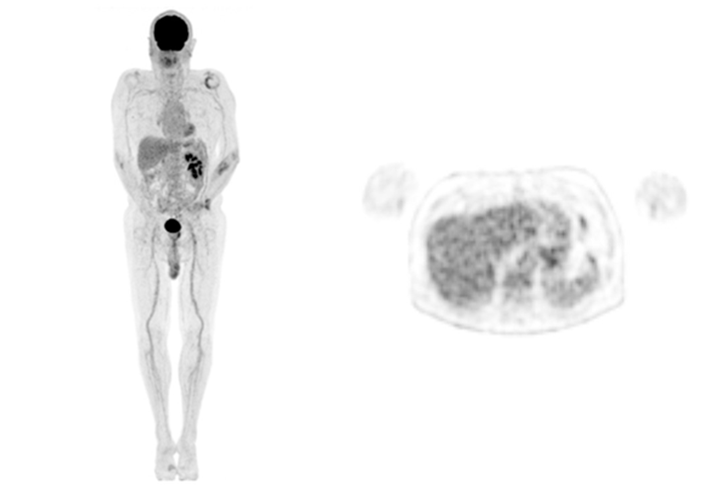

Secondly, in terms of image quality, our team has seen first-hand the major step up from analog to digital cameras and the progressive image improvement with successive iteration of UIH's AI algorithm. This is particularly striking when the same patient returns for their follow-up studies (see Figure 1-3) on the different platforms.

Figure 1. Whole body maximum intensity projection and axial image of a patient with metastatic renal cell carcinoma scanned on the now decommissioned analog PET/CT (injection dose: 242 MBq of 18F-FDG, 60 min uptake time, scan time: 2 min/bed position)